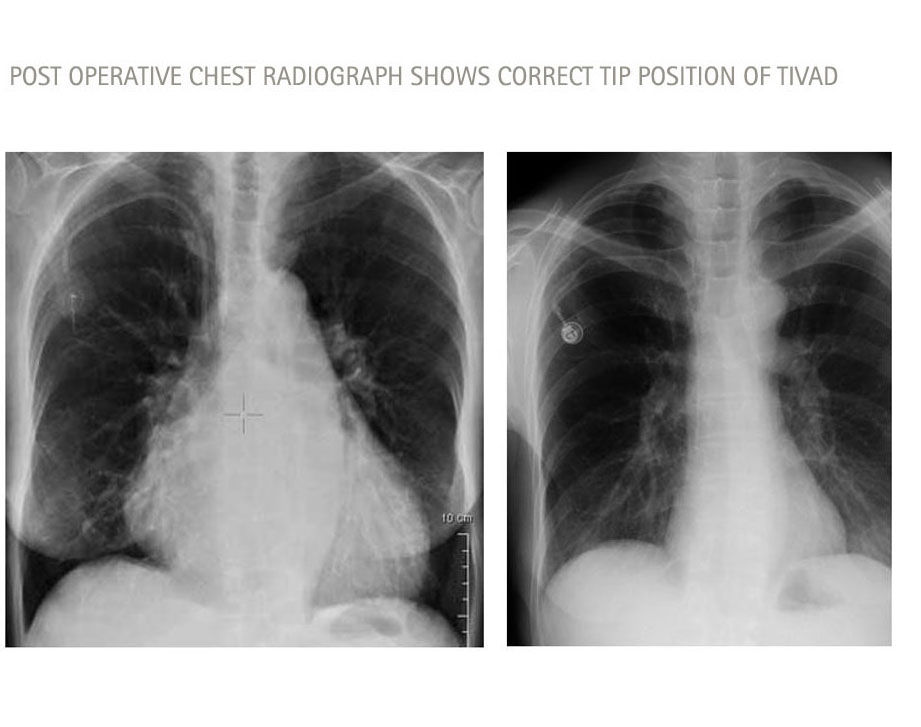

Correct catheter tip positioning6

„ [...] correct position of the catheter has to be ensured during placement"

GroupThrombosis Rate

Catheter tip in upper SVC Left sided port8/28 (28.6%)

Catheter tip in upper SVC Right sided port1/33 (3%)

Catheter tip in lover SVC Left sided port0/250

Catheter tip in lover SVC Right sided port1/68 (1.5%)